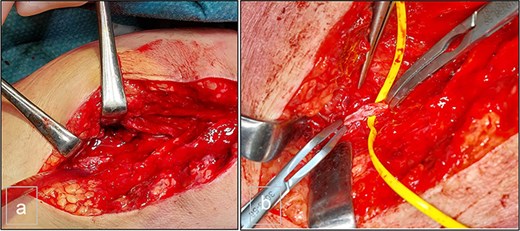

Surgical intervention was performed, consisting of open resection of the pseudoaneurysm at the proximal portion of the PTA, followed by patchoplasty with an autologous vein graft from the homolateral limb. The posterior tibial vein was ligated during the procedure (Fig. 3).

(a) Preoperative view. (b) Preoperative view. PTA after resection of the pseudoaneurysm and before the autologous patchoplasty.